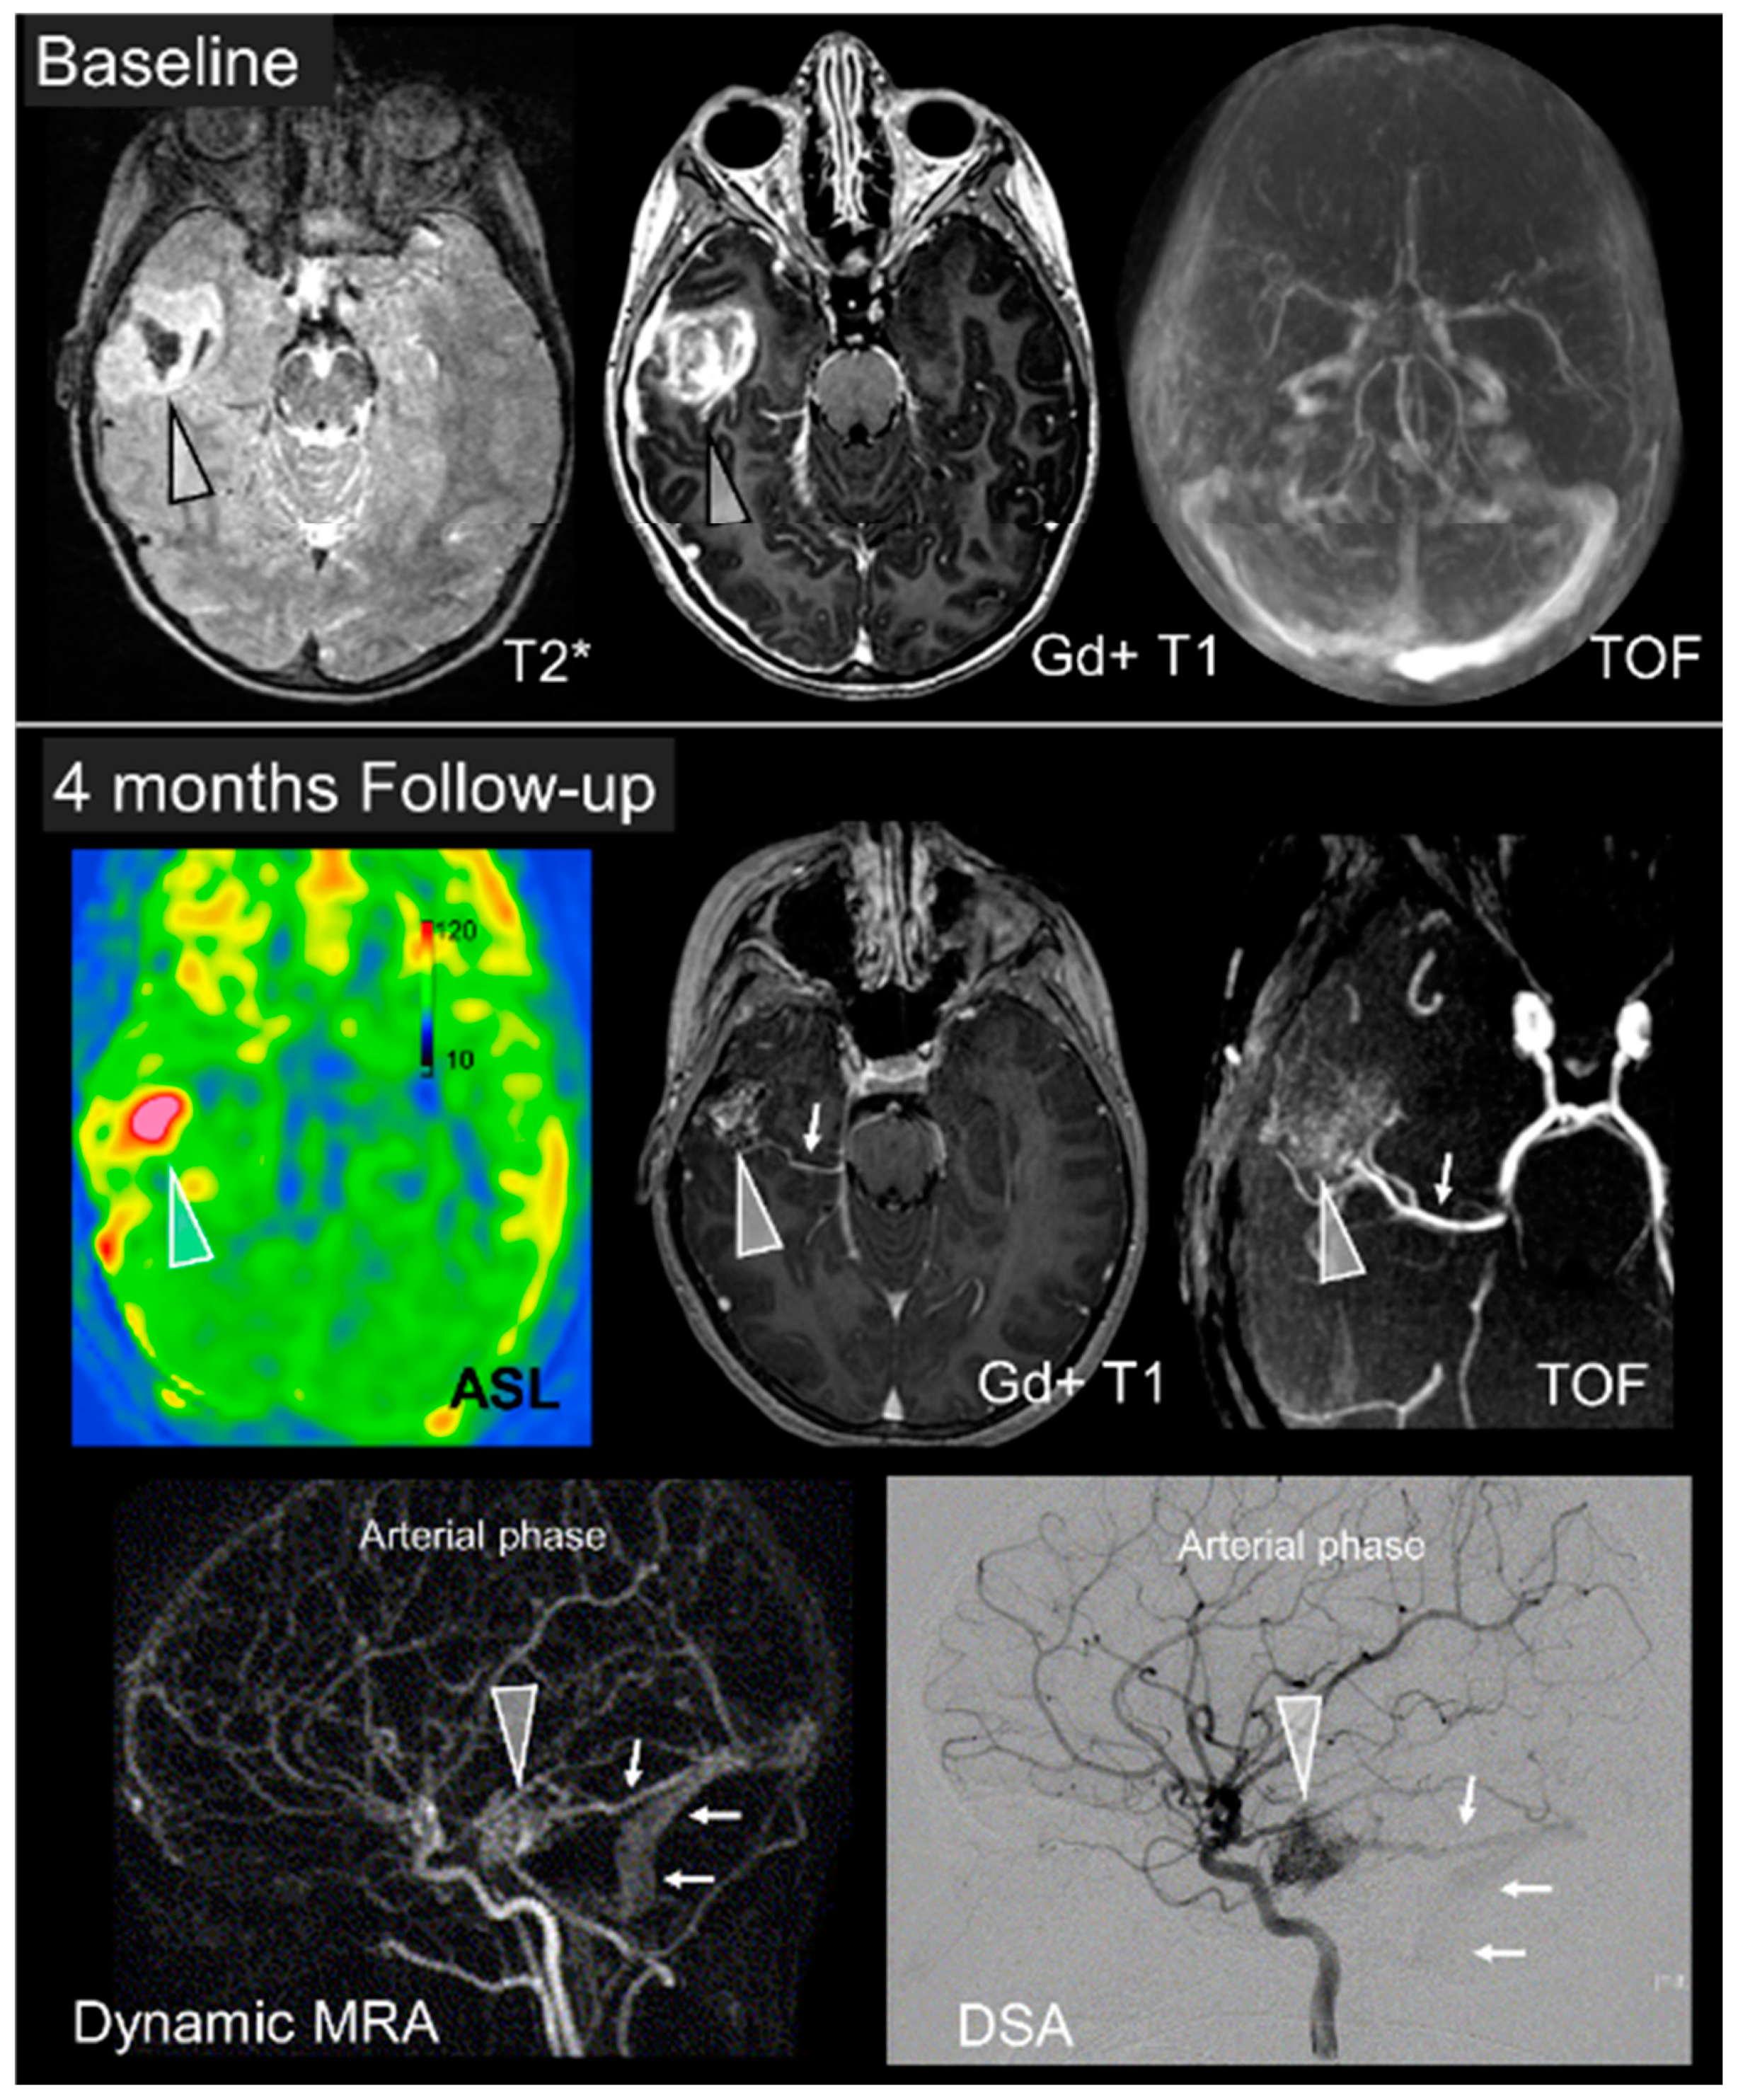

Intracranial vascular imaging (CT or MR angiography) should then systematically be acquired as part of the initial diagnostic examination. Indeed, there is a high prevalence of readily identifiable vascular lesions such as arteriovenous malformations (AVM), arteriovenous fistulas (AVF), or aneurysms in children with ICH. (Figure 1) If identified, high recurrence risk sectors (ectasia or arterial aneurysm) should be searched for so as to guide therapeutic management, and prevent early recurrent bleeding [17].

Digital subtraction angiography (DSA) has a central role for further characterization of vascular anomalies, and to investigate ICHs with undetermined etiology, due to its higher spatial and temporal resolutions and consequent higher sensitivity for intracranial shunts detection. (Figure 1 and Figure 2) The optimal timing for DSA realization is unknown, but should theoretically be performed as soon as possible in children with ICH of unknown origin to identify and treat occult vascular malformations. Of note, DSA is a low risk and often high yield examination in children: a recent analysis of pediatric patients revealed a 0% complication rate during the procedure and a 0.4% postprocedural complication rate [21,22].

Figure 1. Pediatric intracerebral hemorrhage (ICH) main etiologies. (A) Left cerebellar mid peduncular hemorrhage, demonstrated on computed tomography (CT) and CT-angiography; digital subtraction angiography (DSA) (right and inset) shows malformative vessels with PICA and AICA feeders, a nidus and deep venous outflow corresponding to an arteriovenous malformation. (B) Left internal capsule cavernoma, with distinctive heterogeneous signal on T1 (left) and hyposignal on T2 * (right). (C) Smaller ICH in the cerebellar vermis (arrowhead). DSA shows a fusiform, likely dissecting, aneurysm. (D) Clotting factor deficiency revealed by a left supratentorial bleed. The presence of a fluid level is suggestive of a coagulation deficit. (E) Hemorrhagic transformation of a large right hemispheric ischemic stroke.